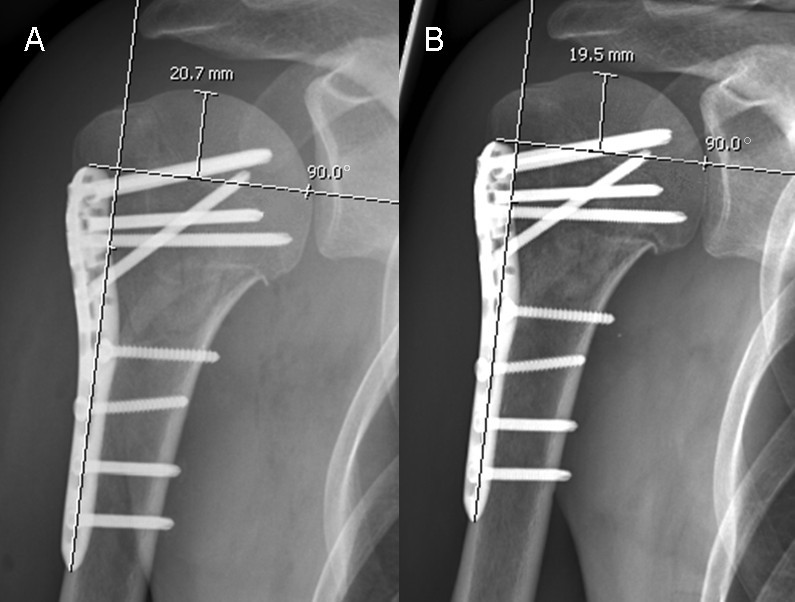

AP (A) and lateral radiographic images (B) of left twopart proximal... Download Scientific Humerus Fracture Screws After surgery, you won't need a. proximal humerus fractures are common fractures often seen in older patients with osteoporotic bone following. humeral shaft fractures are common fractures of the diaphysis of the humerus, which may be associated with radial nerve injury. if you have an open fracture, which involves a piece of bone sticking through your skin,. Humerus Fracture Screws.